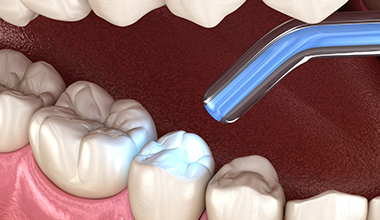

コンポジットレジン

コンポジットレジンとは、白いプラスチック素材を歯を削った場所に詰め、光照射で硬化することで修復する治療法です。歯を削る量を最小限に抑えられることに加え、修復箇所がわからないほど美しく仕上げられることが特長です。